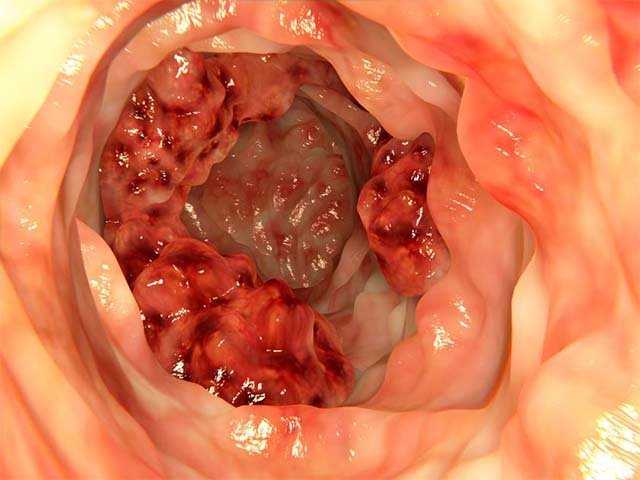

- پولیپ های کولورکتال: پولیپ ها در دیواره داخلی روده بزرگ یا رکتوم رشد می کنند. در مردان بالای ۵۰ سال شایع می باشد. غالب پولیپ ها خوش خیم (غیرسرطانی) می باشند ولی برخی از پولیپ ها (آدنوما) سرطانی می شوند. شناسایی و خارج کردن پولیپ ها، خطر بروز سرطان کولورکتال را کاهش می دهد.

- پولیپ های آدنوماتوز فامیلی که ارثی بوده و نادر می باشد و در اثر تغییر در ژن مشخصی به نام APC ایجاد می شود، در این حالت صدها پولیپ در رکتوم و کولون ایجاد می شوند که در صورت عدم درمان در ۴۰ سالگی، سرانجام به سرطان کولورکتال منجر می شوند. این نوع سرطان ۱% از کل موارد سرطان کولورکتال را تشکیل می دهد.

کولونوسکوپی زمانی مثبت در نظر گرفته می شود که پزشک پلیپ یا بافت غیر عادی در روده پیدا کند. بیشتر پلیپ ها به صورت سرطانی نیستند اما برخی از آنها می توانند پیش سرطانی باشند. پلیپی که در طول کولونوسکوپی از بدن خارج می شود، برای انجام آنالیز به آزمایشگاه فرستاده می شود. بسته به اندازه و تعداد پلیپ ها، ممکن است نیاز به پیروی از یک برنامه غربالگری دقیق تر در آینده داشته باشید.

اگر پزشک شما یک یا دو پلیپ کمتر از ۱۰,۱۶ میلی متری پیدا کند، تکرار آزمایش در هر ۵ الی ۱۰ سال کافی است. اگر پلیپ های شما بزرگتر باشد، پزشک شما ممکن است کولونوسکوپی دیگری را در هر سه الی پنج سال پیشنهاد کند. این مورد نیز بستگی به فاکتورهای خطر دارد. اگر پلیپ های سرطانی در طول کولونوسکوپی برداشته شود، پزشک شما ممکن است پیشنهاد انجام کولونوسکوپی را در هر سه الی شش ماه یکبار دهد. اگر پلیپ یا سایر بافت های غیر عادی وجود داشته باشد که از طریق کولونوسکوپی برداشته نشود، ممکن است پزشک تکرار آزمایش را توصیه کند.